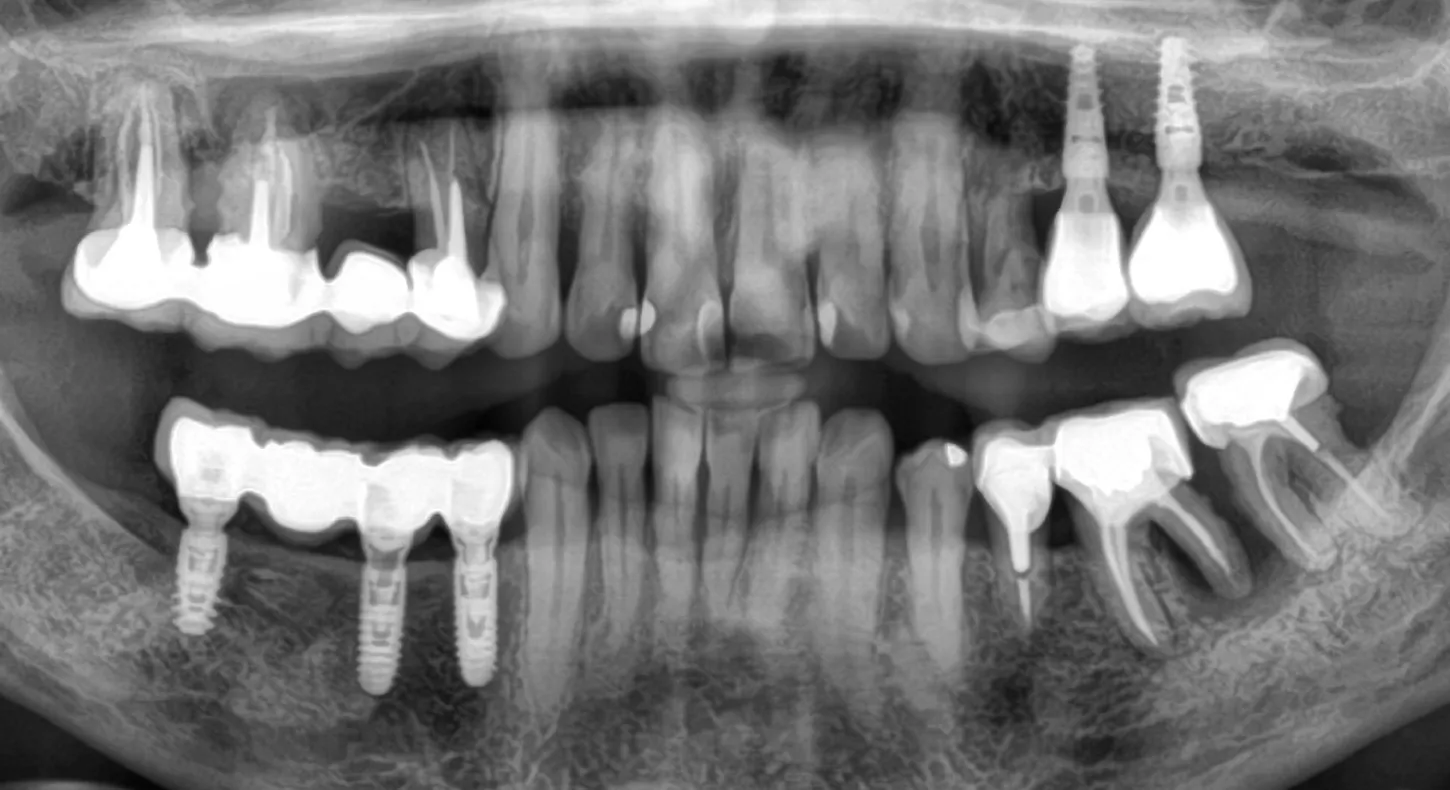

18. 3 years follow up panoramic radiograph.

Two single-unit zirconia-veneered Simeda® crowns were fabricated on titanium bases.

19. Final prosthesis in the mouth 3 years post implant placement.